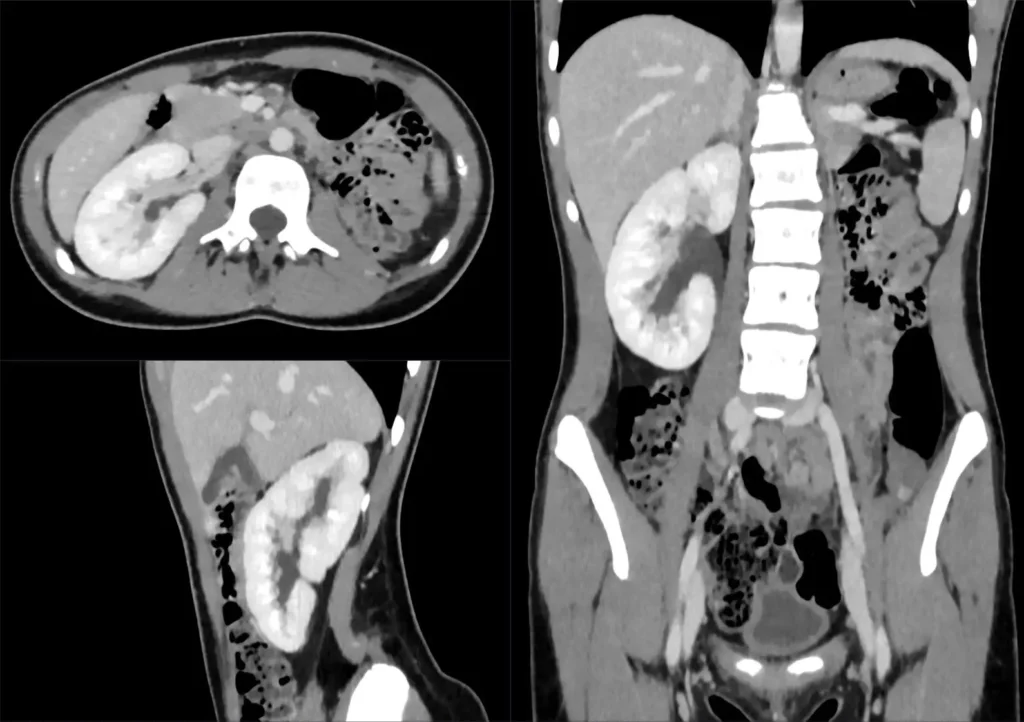

- Computertomographie (CT): Eine CT kann detaillierte Bilder der Nieren und der Harnwege liefern.